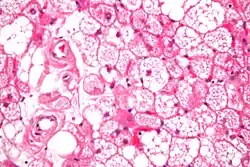

A high power hematoxylin and eosin stained photograph of a hibernoma.

The tumors histologically resemble brown fat. There are four histologic types recognized, but one is the most frequently seen (typical). There is a background of rich vascularity.

1. Lobular type: Variable degrees of differentiation of uniform, round to oval cells with granular eosinophilic cells with prominent borders, alternating with coarsely multivacuolated fat cells (pale cells). There are usually small centrally placed nuclei without pleomorphism. The cells have large cytoplasmic lipid droplets interspersed throughout.[4][5]